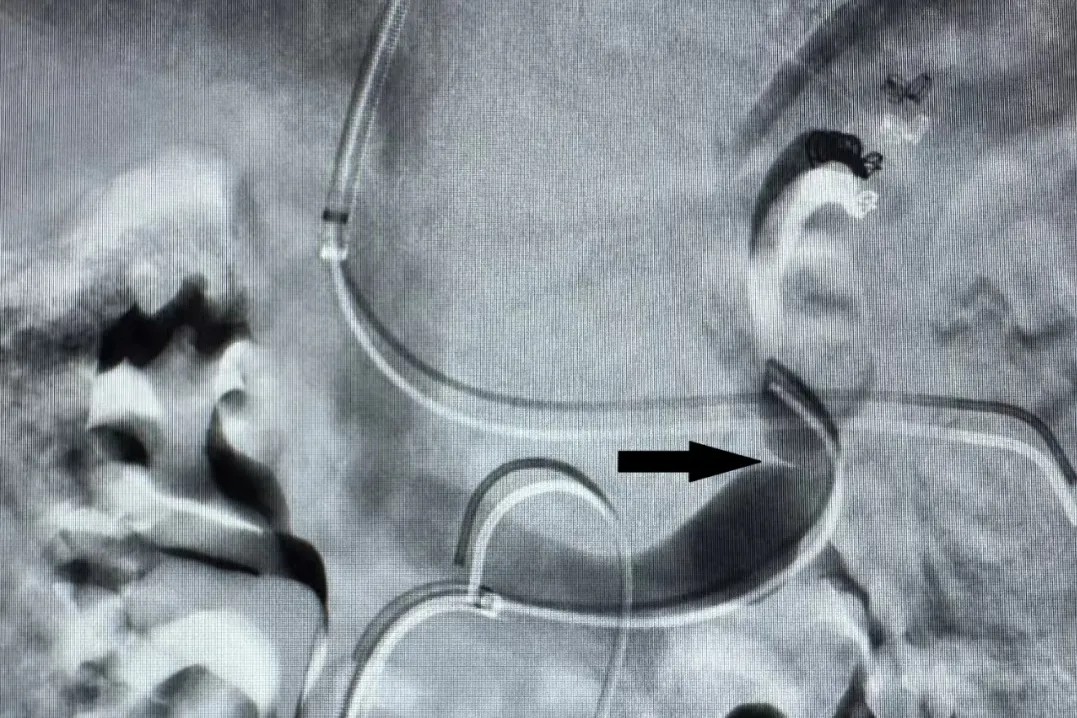

造影显示明显的脾肾分流(黑色箭头)